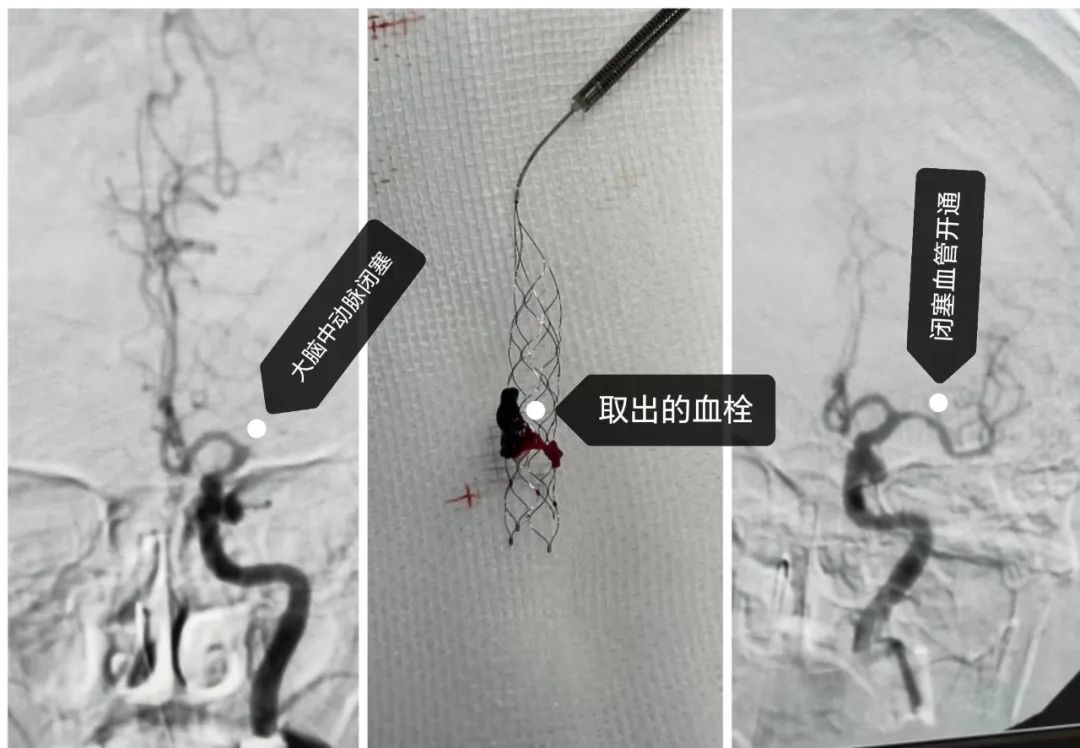

一位85岁女性患者因“皮肤疱疹”入院,住院期间突发失语、右侧侧肢体偏瘫、意识不清等急性脑前循环大血管闭塞症状。NIHSS评分20分(美国国立卫生院神经功能缺损评分),头部CT检查结果排除脑出血,MRA显示左侧大脑中动脉未显影。脑病科、神经外科相关专家会诊考虑为左侧大脑中动脉急性闭塞,立即启动我院“卒中绿色通道”,迅速将患者转至重症医学科,在家属签署相关知情同意书后,卒中团队即刻进行了静脉溶栓治疗,同时做好血管内治疗准备。溶栓后,患者神经系统症状改善不明显,卒中中心立即启动血管内治疗绿道流程,对患者进行脑血管造影(DSA),评估血管情况,发现左侧大脑中动脉仍未开通。 如不及时进行取栓治疗,面临的将是严重偏瘫、昏迷、植物状态等严重后果,甚至威胁生命,在与患者家属沟通后,便准备施行机械取栓术。

脑血管内机械取栓这是一个较为复杂的介入手术。医疗处屈小元副处长组织协调相关科室,术前制定周密细致的手术方案,在导管室和麻醉科的密切配合下,为患者成功实施了“血管内机械取栓术”,将闭塞的大脑中动脉起始段的栓子通过专业的取栓支架取出体外,成功开通受阻血管,使其恢复正常血流,整个手术过程顺利,术后头部CT显示无颅内出血。该患者在术后神经系统症状明显改善,术后第二天意识清楚,讲话语言流利,右侧侧肢体肌力由术前2级恢复至4级。